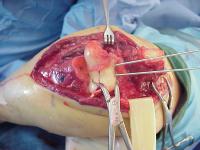

Open reduction via olecranon osteotomy.  The ulnar nerve is  retracted with a penrose drain. The articular surface was reconstructed, then secured to the shaft. After recovering the rotated anterior articular fragment, the anterior and posterior halves of the central articular component were secured with .062" pins. These pins were replaced one at a time with Herbert screws.

Later in the case, the small medial osteochondral fragment was secured with absorbable sutures (not shown).